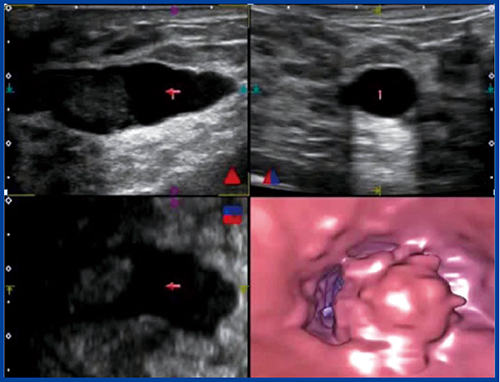

乳管内視鏡検査や乳管造影検査は,侵襲性が比較的高く,手技に熟練を要し,施行できる施設も限定される。そこでわれわれは,乳管への新しいアプローチ法として,乳管内に視点を置き,管内を移動しながら詳細な観察が可能なバーチャル乳管内視鏡の開発を進めてきた(図1)。本講演では,3D乳房超音波検査および「Aplio500」に搭載されたFlyThruによるバーチャル乳管内視鏡の有用性とその進化について述べる。

図1 FlyThruによるバーチャル乳管内視鏡像

乳頭から責任乳管にカニュレーションしてヨード系造影剤を注入し,マンモグラフィを撮影する乳管造影をバーチャルで表現するために,厚みをつけた拡張乳管画像を白黒反転し,低エコーな乳管を立体的な白い構造物として再構成することで,バーチャルな3D乳管造影像が得られる。バーチャル乳管造影では非侵襲的に乳管の拡張,狭小,腫瘤などの所見が得られる。また,バーチャル乳管内視鏡では厚みつき画像で乳管内をのぞき込む形で,乳管外から病変の基部の太さや性状が観察可能であった(図2)。

図2 厚みつき画像によるバーチャル乳管造影・内視鏡像